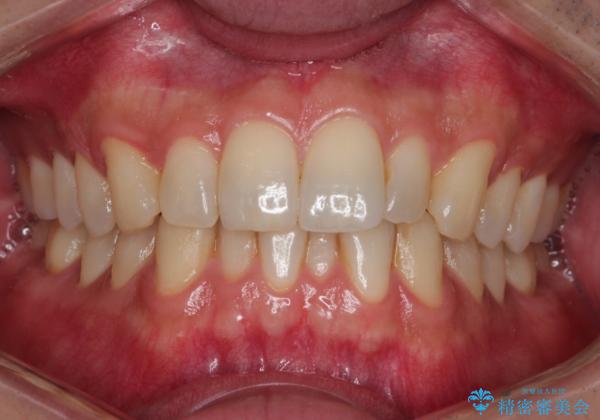

前歯のデコボコした歯並びをマウスピースで改善!

- 前歯の歯並びの改善を希望され来院された患者様です。

矯正装置としてはマウスピースを使用しています。

見た目、嚙み合わせ及び、治療期間や施術内容に大変ご満足いただきました。